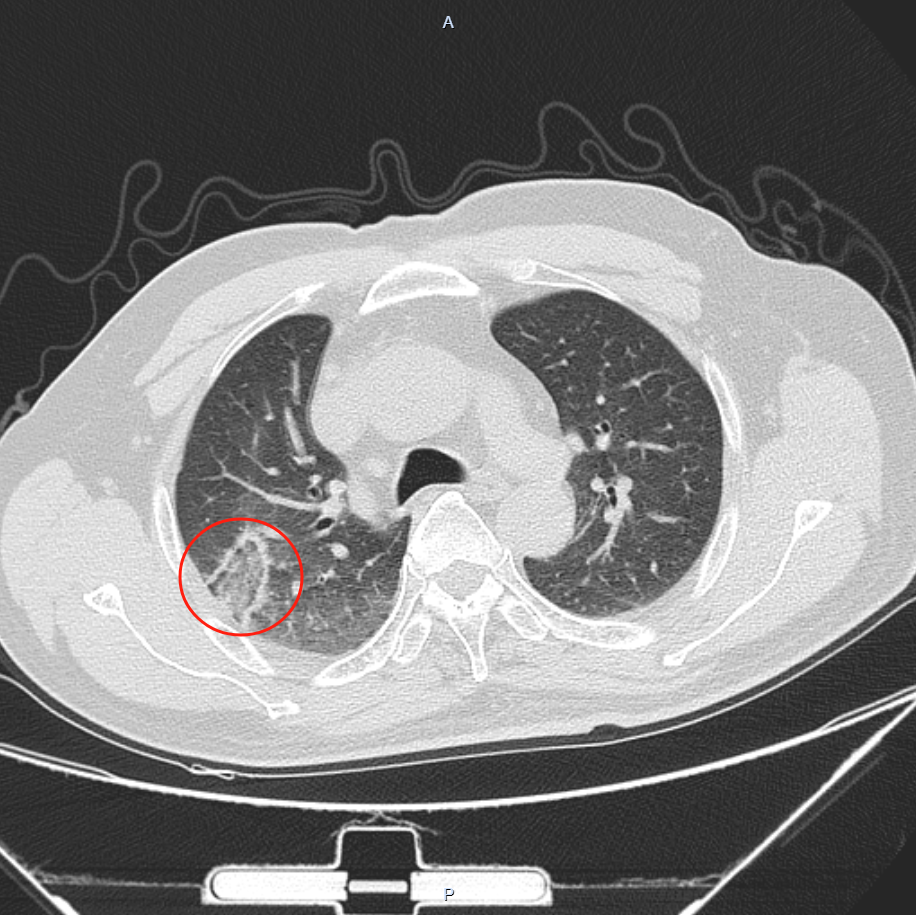

消融前

62岁的钱大爷(化名)在2024年11月进行体检时,查出肺部有结节,因其父亲是肺癌去世,十分焦虑、忧心忡忡,便前往我院肺结节MDT门诊就诊,呼吸与危重症医学科当即组织心胸外科、医学影像科等科室专家进行肺结节多学科(MDT)讨论,该结节有8mm大小并存在滋养血管,患者又有肺癌家族史和长期吸烟史,考虑高危肺结节。